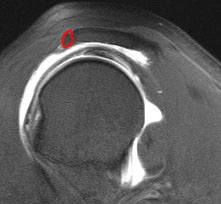

Axial MRI Sagittal MRI

Axial MRI with meso-acromiale